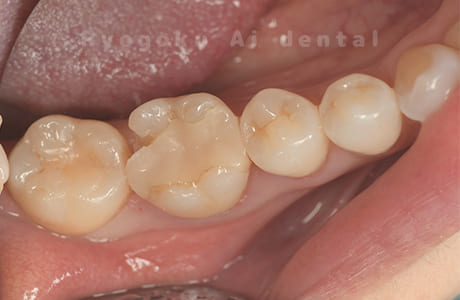

Case11

- 治療内容

- セラミッククラウン、セラミックインレー

- 治療費用

- 123,000円×2(セラミッククラン)、77,000円(セラミックインレー)

銀歯が取れて、ご来院された患者様です。奥歯2本をセラミッククラウン、手前の小臼歯をセラミックインレーで治療を行いました。